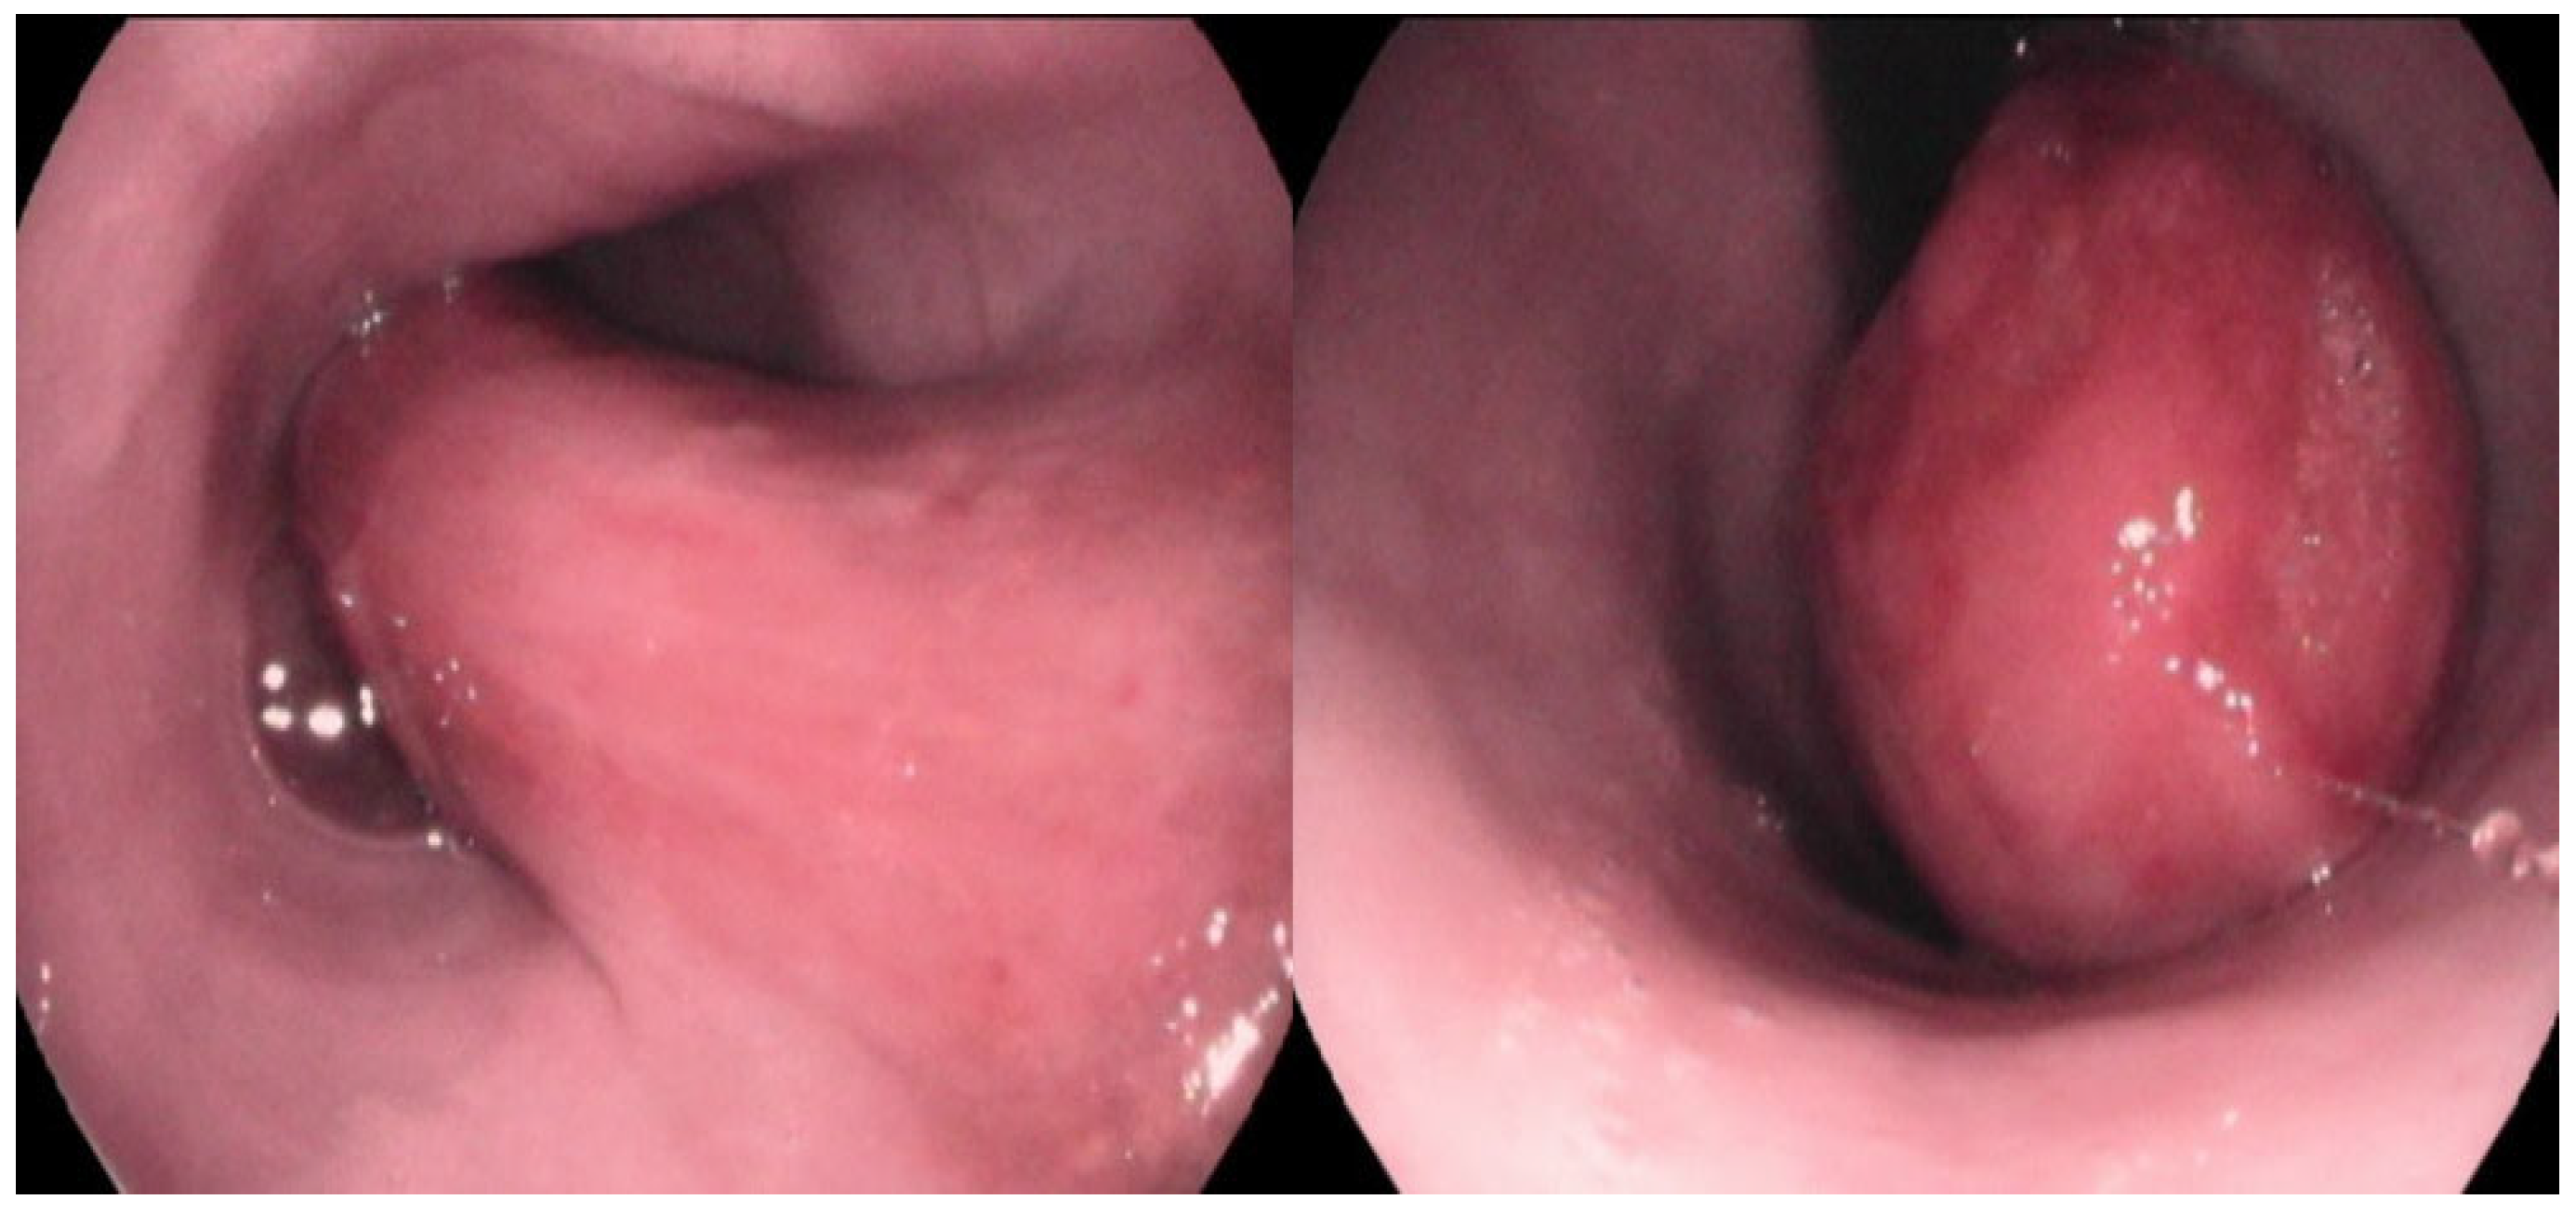

A large, highly vascular, obstructive, solitary mass with a smooth surface was detected (Figure 2). Endoscopic biopsies of the mass were collected for histopathologic examination. Specifically, seven biopsy samples from stomach, eight from duodenum, and eight from the esophageal mass were obtained using a 2.2 mm biopsy forceps. Biopsy samples were placed in 10% neutral buffered formalin and embedded in paraffin until histopathologic examination. The owner was instructed to feed the dog a high-energy, moist, home-made diet fed from an upright position to facilitate esophageal transit until histopathologic results were available.

Figure 2.

Macroscopic view of the esophageal lumen during the esophagoscopy. A large, highly vascular, obstructive, solitary mass with a smooth surface was noted. The mass was located between 1st and 7th thoracic vertebra.

Follow-up esophagoscopies were performed every 3–6 months after surgical excision and did not show evidence of tumor regrowth in the esophagus until 18 months after surgery, when recurrence of the mass was identified (Figure 10). The dog still remains asymptomatic, with the exception of one episode of vomiting and regurgitation, which was resolved after symptomatic treatment.

Figure 10.

Macroscopic view of the esophageal lumen during follow-up esophagoscopy. Notice a regrowth of the mass (18 months after the surgical excision).